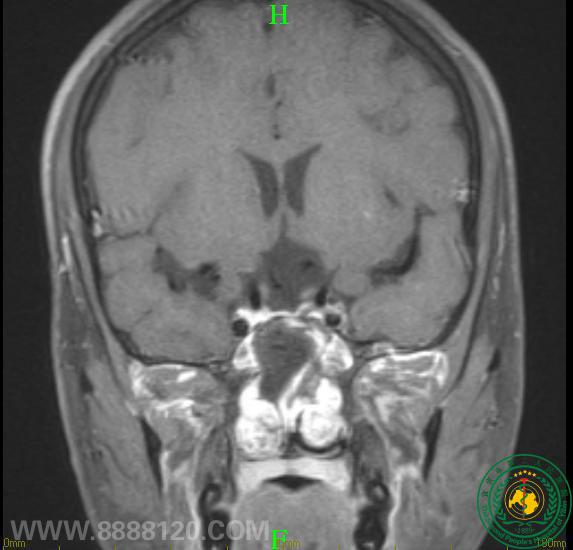

眼睛突然看不清,需警惕是颅内肿瘤作怪

眼睛突然看不清,需警惕是颅内肿瘤作怪15297